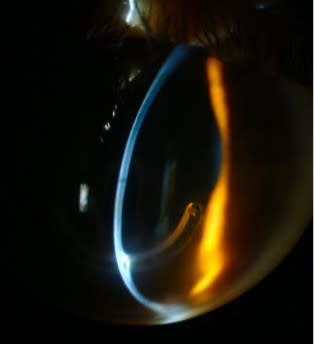

Upon examination, she presented with pellucid marginal degeneration (PMD) in her left eye (Figures 2 and 3). The patient was previously seen by a surgeon who performed an intracorneal ring implant that did not improve her vision. She opted for scleral lens fitting instead of undergoing another surgical attempt. The first attempt to fit her with a scleral lens resulted in significant touch at the lower peripheral cornea that caused discomfort and ocular hyperemia. She was then referred to our clinic, where she was successfully refit with a scleral lens in 2015.

In February 2025, the patient returned to our clinic for care. During the pandemic, the patient was seen elsewhere, and was fit with a 17.0 mm scleral lens, which was smaller than her previous, successfully fit lens. Assessment of this lens revealed mild corneal touch around the lower cornea (Figure 4). The lens also created compression and uneven distribution at the landing zone haptic (Figure 5). The patient was unable to wear it for more than 3 hours. Additionally, the lens power had not been updated following cataract surgery a year earlier.